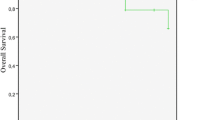

With a median follow-up of 26 months (range: 0–307 months), progression was observed in 58 cases (11%). In univariate analyses, risk of postoperative tumor recurrence was higher in males (HR, 2.10; 95%CI 1.25–3.54; p = 0.005), in high-grade meningiomas (HR, 4.69; 95%CI 2.72–8.07; p < 0.001), and, with borderline significance, after STR (HR, 1.82; 95%CI 1.00–3.32; p = 0.05). Among the analyzed radiological variables, disruption of the arachnoid layer (HR, 2.50; 95%CI 1.36–4.61; p = 0.003), heterogeneous contrast enhancement (HR, 2.05; 95%CI 1.22–3.46; p = 0.007), and an irregular, mushroom-like tumor shape (HR, 2.57; 95%CI 1.51–4.37; p = 0.001) were associated with an increased risk of recurrence (Table 3). Correspondingly, disruption of the arachnoid layer (Fig. 3a, p = 0.002), heterogeneous contrast enhancement (Fig. 3b, p = 0.006), and an irregular tumor shape (Fig. 3c, p < 0.001) were correlated with shorter PFI (see details in legend). Similarly, a rising tumor volume (HR, 1.01; 95%CI 1.00–1.01; p = 0.045) correlated with an increased risk of recurrence (Fig. 3d). ROC analyses revealed an optimal cut-off tumor volume of 11.32 ccm for the prediction of recurrence (sensitivity 0.65, specificity 0.51, AUC = 0.061; p = 0.010). Multivariate analyses adjusted for age, sex, WHO grade, and the analyzed radiological variables confirmed high-grade histology (HR, 4.58; 95%CI 2.41–8.71; p < 0.001), tumor volume (HR, 1.01; 95%CI 1.00–1.02; p = 0.032), and disruption of the arachnoid layer (HR, 2.44; 95%CI 1.21–4.92; p = 0.013) as risk factors for recurrence. No other correlations between any of the analyzed radiological variables and recurrence were found (Table 3).

Kaplan-Meier (a–c) and Box plots (d) showing correlations between radiological variables and progression. Median PFI was 92 months and not reached in patients with an intact or disrupted arachnoid layer on the brain/tumor surface, respectively (a, p = 0.002, log-rank test). Similarly, median progression-free interval (PFI) was 90 months in individuals harboring irregularly shaped tumors, while median PFI was not reached in cases with regularly shaped meningiomas (b, p < 0.001). Median PFI significantly differed between patients with heterogeneous and homogeneous contrast enhancing tumors (c, p = 0.006, medians not reached). In d, Box and whiskers plots illustrate that the median tumor volume was higher in patients with than without developing recurrence during follow-up (18.72 ccm, range 0.70–267.77 ccm vs 10.71 ccm, range 0.02–356.94 ccm; p = 0.010). The boxes indicate upper and lower 25% quartile, the whiskers the minimum and maximum value, the dots the outliers, the asterisks the extreme values, and the heavy horizontal line indicates the median (*statistically significant, ccm cubic centimeter)

Subgroup analyses of 132 patients (23% of the entire collective, including 92 females, 70%, and 40 males, 40%; median age 54 years; 110 WHO grade I, 83%, and 22 grade II/III tumors, 17%) with at least 5-year follow-up after surgery confirmed disruption of the arachnoid layer (HR, 3.43; 95%CI 1.52–7.75; p = 0.003), heterogeneous contrast enhancement (HR, 2.16; 95%CI 1.13–4.14; p = 0.020), and an irregular tumor shape (HR, 2.56; 95%CI 1.31–5.00; p = 0.006) to be strongly correlated with progression. In multivariate analyses, GTR (HR, .26; 95%CI .09–.76; p = 0.013), hyperintensity on T2-weighted imaging (HR, 0.31; 95%CI 0.13–.78; p = 0.012), and intratumoral calcifications (HR, 0.14; 95%CI 0.04–.55; p = 0.005) were predictors for lower risk of recurrence, while high-grade histology (HR, 5.15; 95%CI 1.93–13.72; p = 0.001), and, most significantly, disruption of the arachnoid layer predicted tumor relapse (HR, 9.41; 95%CI 2.97–29.80; p < 0.001).